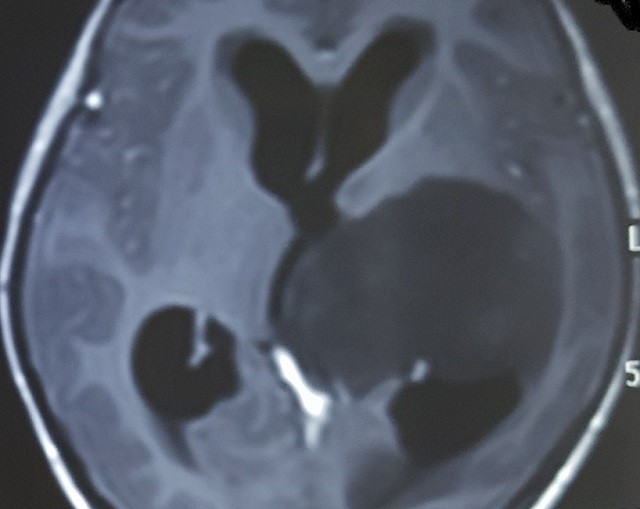

Hình ảnh phim chụp u tế bào thần kinh đệm của bệnh nhân. (Ảnh:BSCC)

Trao đổi với PV báo ANTĐ, PGS.TS - BS Đồng Văn Hệ, Phó Giám đốc bệnh viện Việt Đức cho hay, cháu bé kể trên đã được bố mẹ đưa đến bệnh viện Việt Đức cách đây vài tháng và được chính ông chẩn đoán mắc u tế bào thần kinh đệm (u xảy ra ở não và tủy sống). Qua thăm khám, BS Hệ đã khuyên người nhà bệnh nhân cho mổ để cắt khối u càng sớm càng tốt.

Chia sẻ trên báo Nhân dân, BS Hệ cho biết thêm, u tế bào thần kinh đệm là khối u xảy ra ở não và tủy sống. U thần kinh đệm này bắt nguồn từ các tế bào dính kết hỗ trợ (những tế bào thần kinh đệm) – loại tế bào này bao quanh các dây thần kinh và giúp chúng thực hiện chức năng của mình.